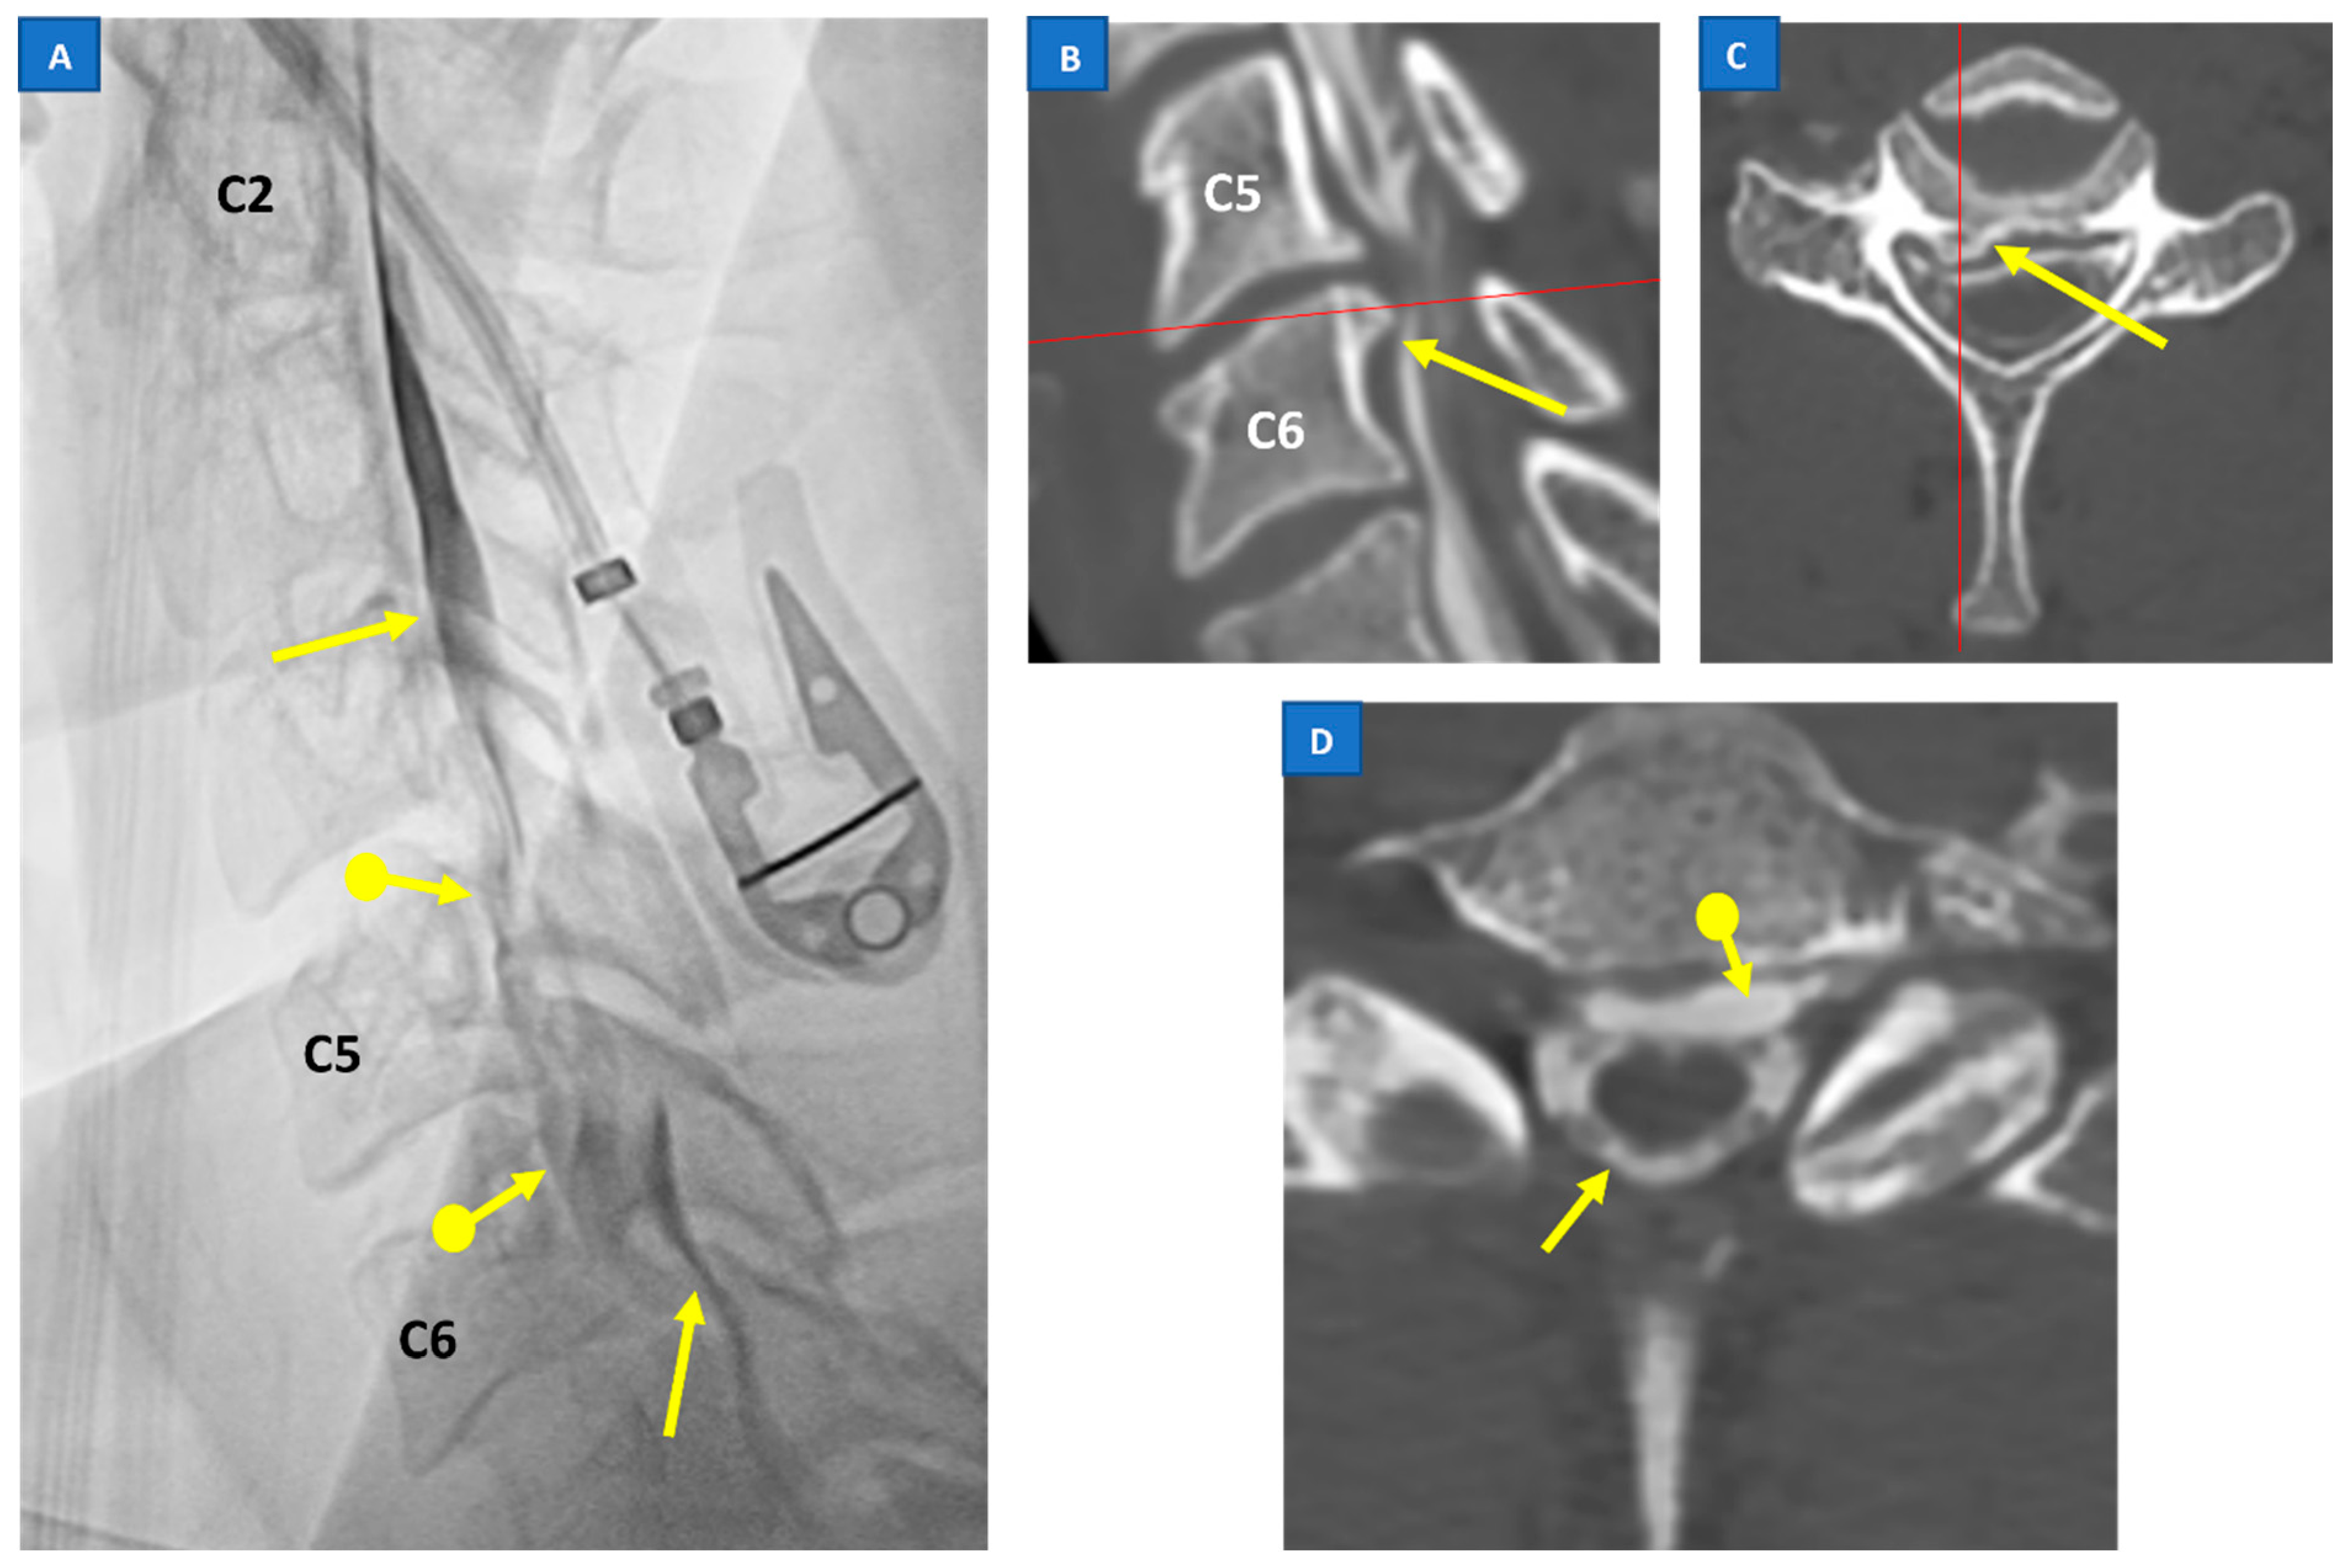

5.3. Digital Subtraction Myelography (DSM)

5.4. CT Myelography